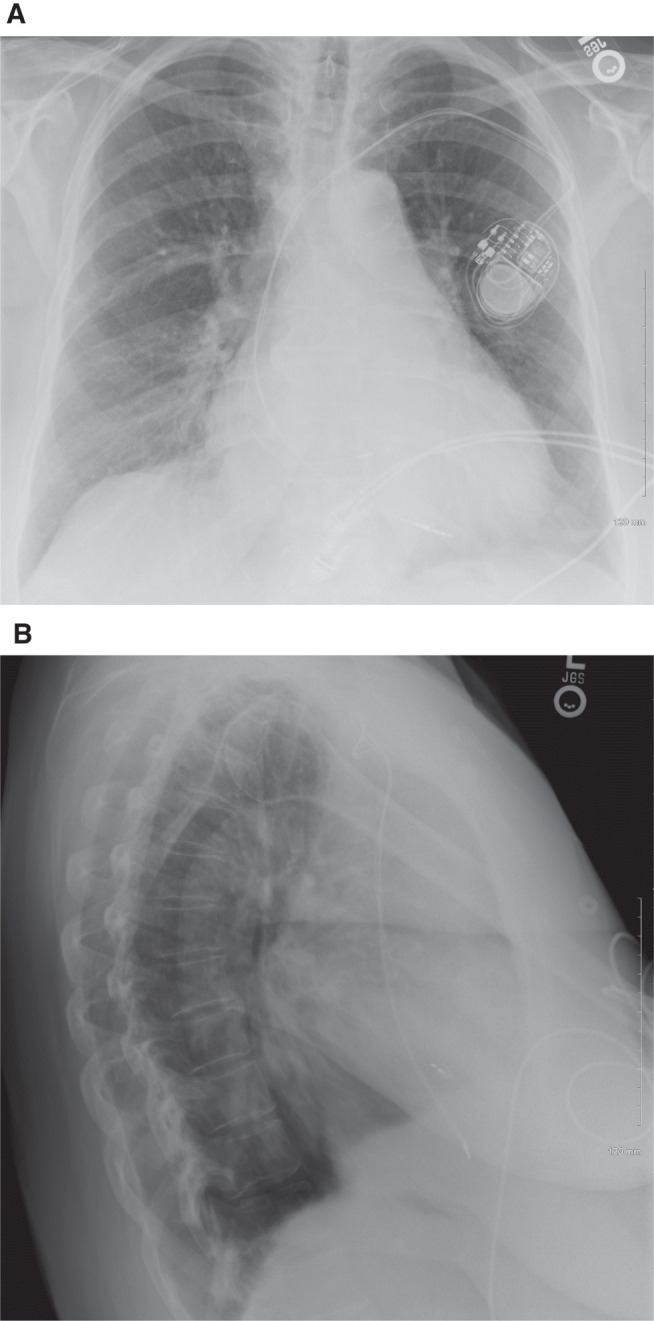

传导系统起搏是一种实现心脏生理性起搏的新型起搏技术,但其在同时消融房室结的心房颤动患者中的实用性和安全性似乎尚不清楚。在这里,我们报告了10例长期持续性或永久性房颤患者的病例系列,他们的控制率治疗失败,并选择同时进行房室结消融和his束起搏器植入。

Conduction system pacing has emerged as a new pacing technique to achieve cardiac physiologic pacing, but its utility and safety in patients with atrial fibrillation undergoing simultaneous ablation of the atrioventricular node remains seemingly unknown. Here, we present a case series of 10 patients with long-standing persistent or permanent atrial fibrillation who failed rate-control therapy and elected to proceed with simultaneous ablation of the atrioventricular node and His-bundle pacemaker implantation.